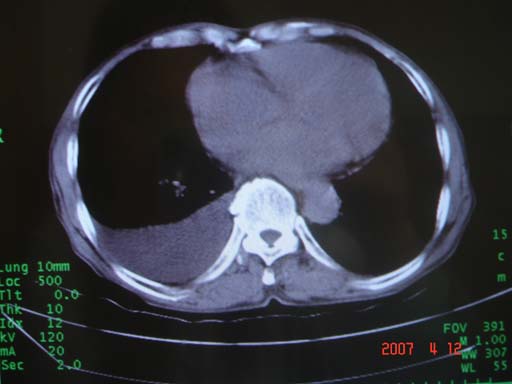

帮我 看看。男77岁咳嗽咯血2月发热2周!病人一般情况可 口痰为鲜红,有点象洗肉水(我看见他吐的痰了)

考虑右肺新生物伴右中上肺阻塞性肺炎及含气不良,右侧胸腔积液。建议痰与纤支镜检查

病灶局限在右肺中上叶,呈大片状实变影,内见空气支气管征,支气管分支较柔软,纵隔内未见肿大淋巴结.支持:感染性病变_1 大叶性肺炎.2 干酪性肺炎.

优先考虑右上肺干酪性肺炎并同侧中叶播散、胸腔积液。分析:右膈肌未见升高、纵隔未见明显右移,胸部各组淋巴结未见可疑肿大,中叶可见支气管铸形,肺野、肺门未见可确定肿块。

支持右侧大叶性肺炎、右侧胸腔积液。建议严格抗炎治疗后复查或支气管镜检进一步检查。

有点象洗肉水的痰,其来源应当是实变引起的血细胞渗出导致,可见支气管气象,实变区有虫蚀状空洞,有明显胸腔积液,未见明显肺门区肿块影,考虑继发型肺结核,干酪性肺炎

右肺上叶实变,实变范围如此之大,如果用肺癌解释的化,应该是比较大的支气管开口发生完全阻塞,但观察上叶前后段支气管还是比较通畅,所以应考虑感染性病变,大叶性肺炎可能,建议抗炎治疗后复查。

考虑右中上叶大叶性肺炎,右侧胸水。抗炎治疗后复查。